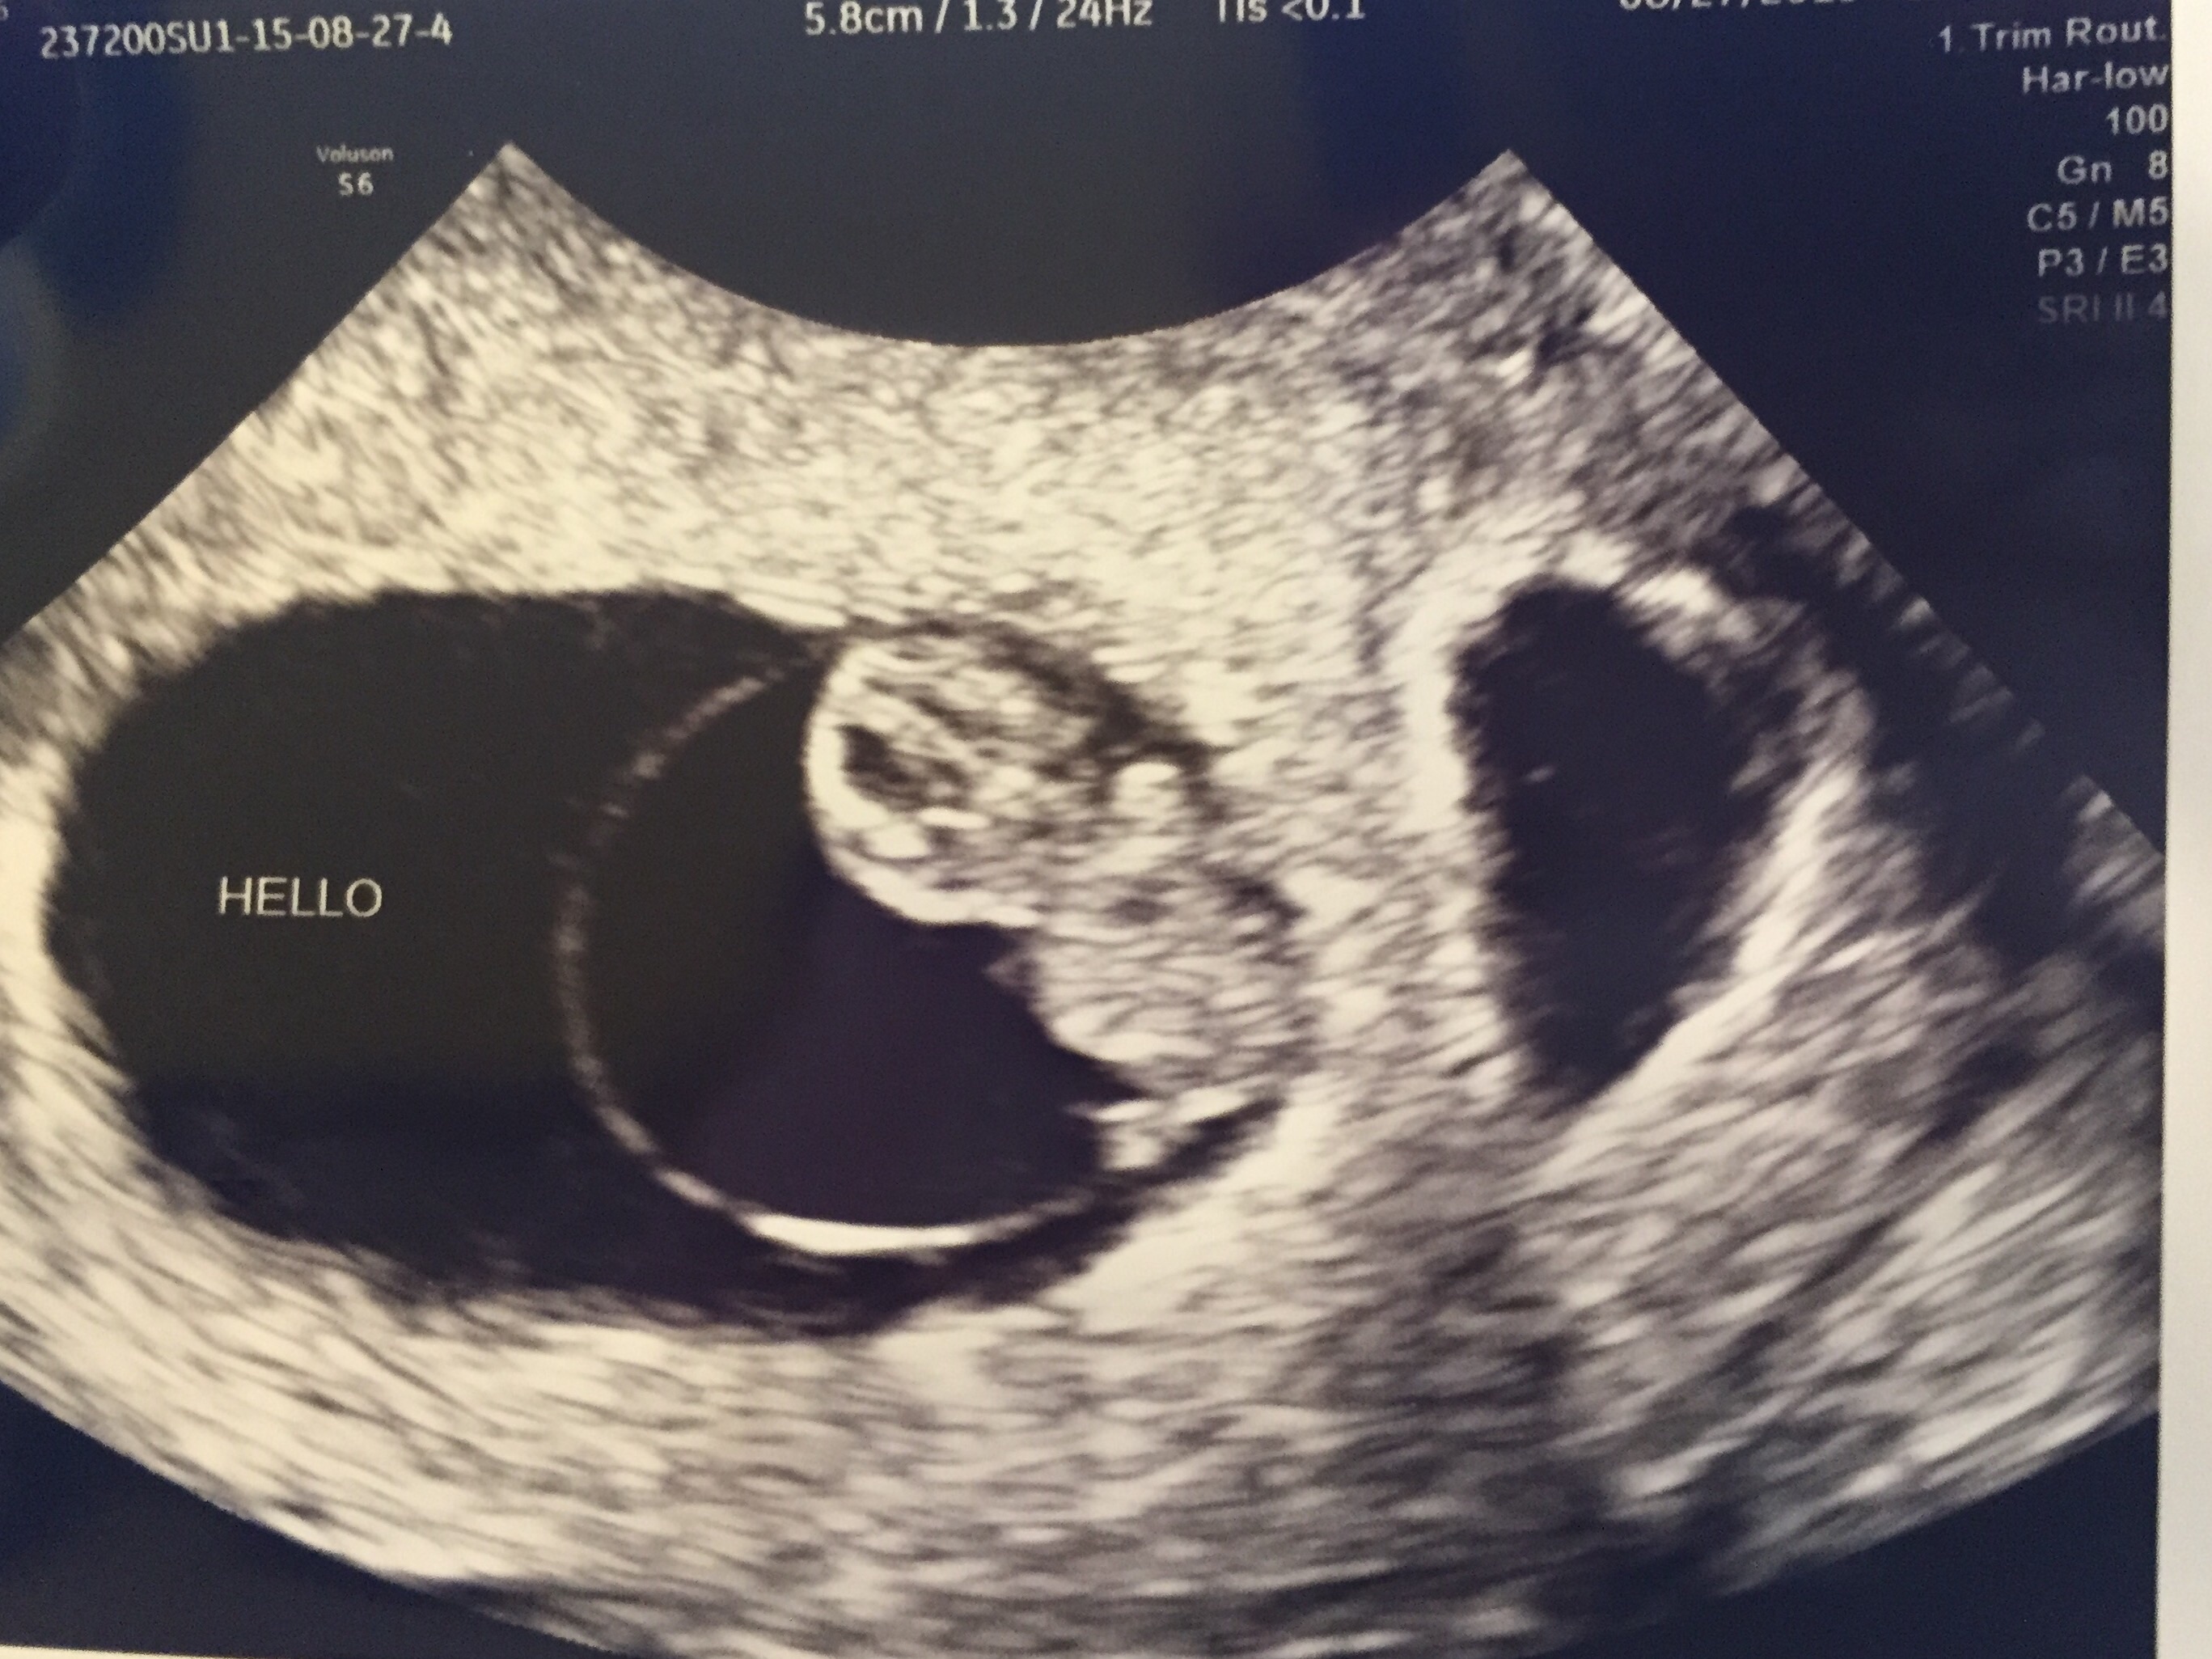

Had an unexpected US today due to some cramping. I was so expecting the worst... I am my own worst enemy but, baby has once again doubled in size from last Friday 8.21.15 to today 8.28.15!! Heartbeat today was up from 165 to 182!!!! We also got to see he/she wiggle which brought tears to my fiancées eyes... And in turn I cried. Tears of joy!! Keeping all of you in my thoughts! Positive vibes your way!